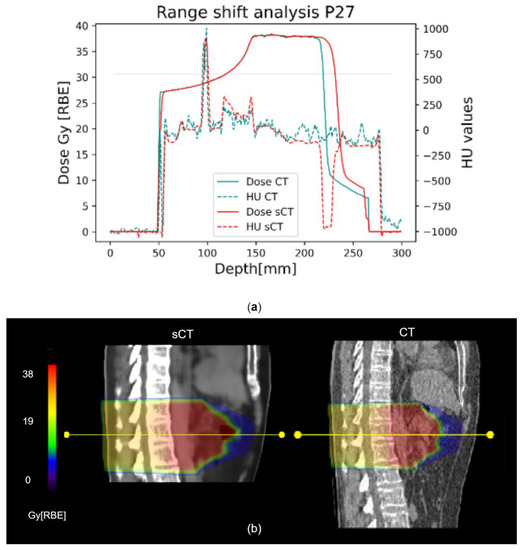

3. Results

4. Discussion